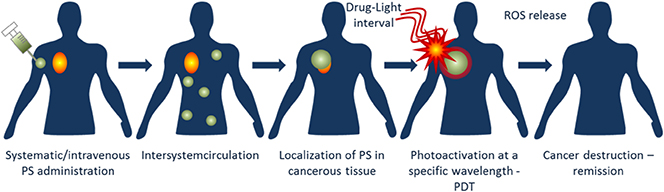

NIMMS (Next Ion Medical Machine Study). https://www.hitriplus.eu/ Heavy Ion Therapy Research Integration plus.